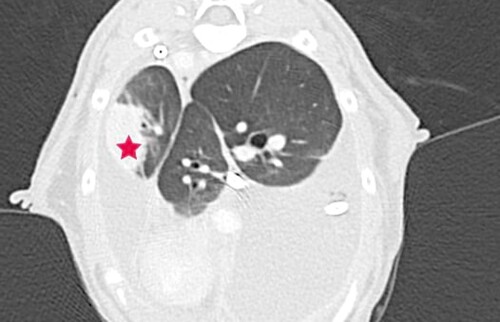

Merlin konnte nach erneuter Thora­ko­zen­tese mittels Thoraxkatheter, Therapiestart mit Rutin, Prednisolon und Buprenorphin zwei Tage lang stabil gehalten werden. Dann zeigte er erneut eine abdominal betonte Tachypnoe mit verschärftem Atem­geräusch. Sonographisch ließ sich ein bilateraler hgr Thoraxerguss sowie eine sehr verdickte und gewebige Pleura darstellen. Diese Befunde konnten in der anschlie­ßenden Computertomographie bestätigt werden, zusätzlich stellte sich der Ln. Sternalis mgr. vergrößert dar und im linken caudalen Lungenlappen war eine struk­tu­relle Veränderung zuerkennen (hypo­attenuierte, intraparenchymal, Kontrastmittel aufnehmend). (Abb. 1-3)

Verdickte Pleura (Pfeile)

Abb. 2 verdickte Pleura (Pfeile)